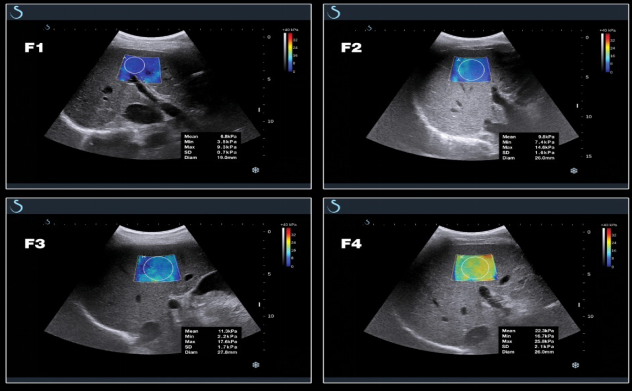

E成像(SWE)實時剪切波彈性成像技術(shù)

“聲藍”獨有的E成像(SWE)實時剪切波彈性成像技術(shù)可以廣泛應(yīng)用在實性臟器腫瘤的早期檢出和鑒別診斷、定量評估、介入穿刺引導(dǎo)、各類疾病治療前后的評價等,也是唯一全面通過美國FDA認證的實時、全幅、全定量的組織硬度可視化測量模式,因而為臨床診斷和治療,提供了安全、無創(chuàng)、有效的最新影像學全新檢查方法。目前已被應(yīng)用于甲狀腺、乳腺、肝臟、腎臟、前列腺、腸管、淋巴結(jié)、肌肉骨骼、軟組織等全身器官的鑒別診斷和定量評估。

彈性超聲與以往普超聲相比,相當于“深觸診”,可以更加直觀地“接觸到”軟組織的形態(tài),并且速度可達到1厘米/秒。與此同時,它的畫面是連續(xù)性的,具有以往單點式的超聲設(shè)備無可比擬的優(yōu)勢。它的“彈性”級別也是最高的,特別適應(yīng)于甲狀腺和乳腺的超聲診斷,并且配備了多個探頭,適用于人體不同部位的超聲需求。彈性超聲的引進與應(yīng)用,可對腫瘤的良惡性鑒別診斷及肝纖維化的無創(chuàng)診斷提供重要依據(jù),可明顯提高診斷準確率,具有非常高的敏感性、特異性,提高檢出率,為臨床診斷及治療提供重要依據(jù),盡早為患者爭取最佳的治療時機。